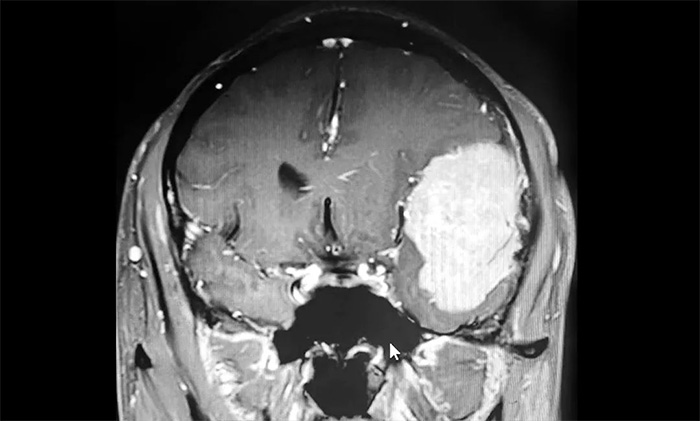

家人将其送往当地医院,经检查,肩胛骨骨折。进一步检查头颅CT,发现其左侧额颞部团块状高密度影,最大直径约6.0公分(厘米)。病灶体积巨大,患者来到上海蓝十字脑科医院寻求进一步治疗。

入院后,患者收治于神经内科4A病区。完善针对性检查后,经多学科综合会诊,患者左侧额颞部实性占位,最大直径约6.0公分,体积如鸭蛋大小,考虑左侧额颞部脑膜瘤。

▲ 肿瘤体积如鸭蛋大小